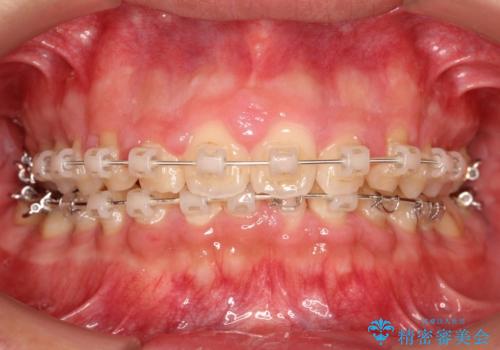

初診時の歯並びの状態としては、上下ともに前歯部の中等度のがたつきがあり、前歯には正中離開があり過蓋咬合を呈してい状態でした。

また奥歯の噛み合わせのズレもあり、特に左は顕著に認められました。

検査の結果、抜歯なし/ワイヤー矯正にて治療を行いました。